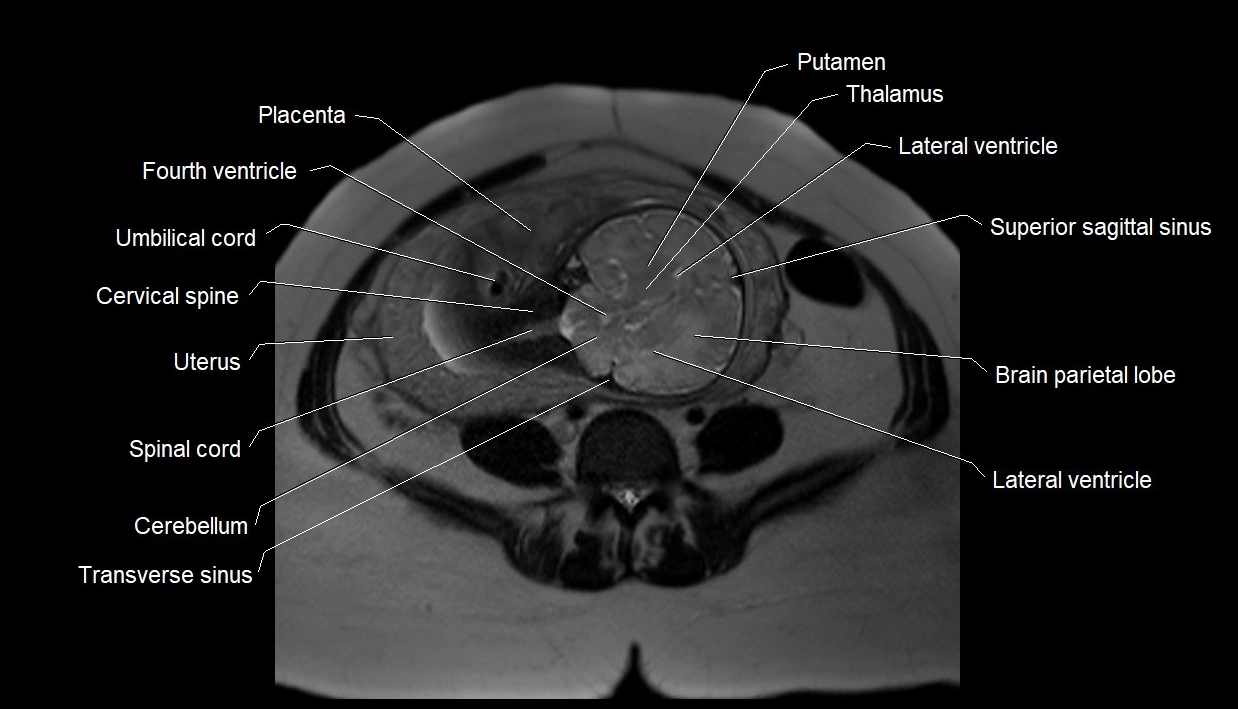

Amniotic fluid is the protective liquid surrounding the fetus within the amniotic sac. It plays an essential role in cushioning the fetus, enabling fetal movement, maintaining temperature stability, and allowing for normal lung and musculoskeletal development.

The volume and composition of amniotic fluid change throughout pregnancy. It is mainly derived from maternal plasma in early pregnancy, while in later stages, it consists largely of fetal urine, lung secretions, and transmembrane exchanges.

• Imaging relevance: MRI used for fetal visualization and assessing oligohydramnios/polyhydramnios when ultrasound is inconclusive

MRI Appearance

T2 HASTE (T2 GRE):

• Amniotic fluid shows very bright hyperintense signal

• Provides natural contrast against fetus and placenta

• Small particles (vernix) may appear as scattered hypointense foci within bright fluid